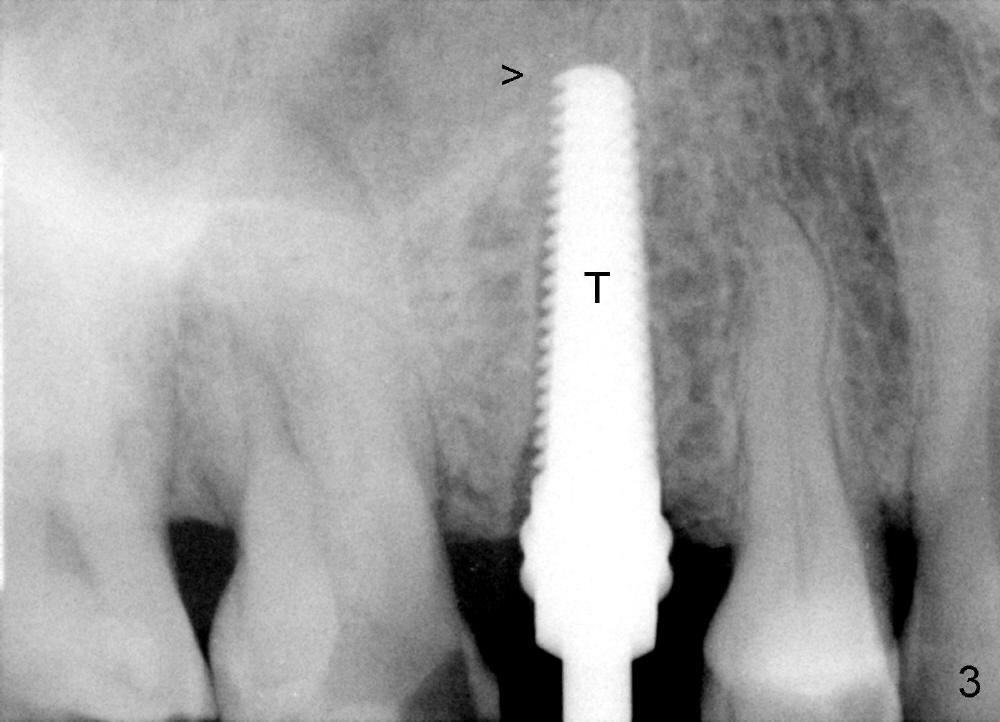

A 72-year-old man is a bruxer with #3 cusp fracture with chronic periapical radiolucency (Fig.1 *) and #4 acute crack. It appears reasonable to take care of emergency (#4 extraction and immediate implant (Fig.3-7: 4.5x20 mm, 45 Ncm)) followed by root canal therapy or extraction for #3. Eight (Fig.8) and 14 (Fig.9-11) days postop, the patient is doing fine and the wound heals normally. But he does not agree any treatment for #3, since it is asymptomatic in spite of a fistula associated with the tooth (Fig.8,9 >). Three months postop, the patient is still asymptomatic and is ready for #4 restoration since the tooth #28 cracks. Follow-up PA shows the persistent distal gap (Fig.12 >, as compared to Fig.4), accompanied with crestal bone resorption (*). Clinically the implant has mild mobility and light tenderness. The patient still refuses #3 treatment. It appears that the implant has failed to osteointegrate. In brief, do not place an immediate implant next to active infection.

Five and a half months postop, the distal gap appears to have reduced (Fig.13 >). Clinically the implant is stable and is ready for restoration. It is advisor able to watch those asymptomatic immediate implants with minimal mobility. It takes time to osteointegrate the immediate implant considering the peri-implant space.